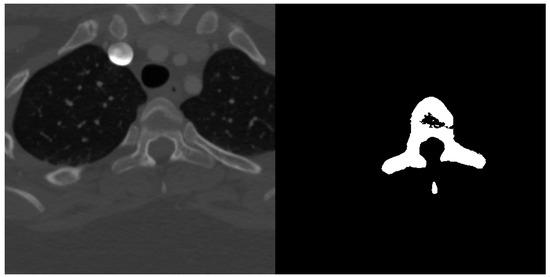

Spine dataset consists of 10 CT scans of different patients in the age 16–35 years old. The pictures had resolution pixels and were provided in NRRD format. Number of slices in each scan was in range from 520 to 600 slices in the third dimension. Scans cover lumbar and thoracic spine region and were acquired without intravenous contrast. Slice thickness is 1 mm per slice and the in-plane resolution is between 0.31 and 0.45 mm. The data have been acquired at the Department of Radiological Sciences, University of California, Irvine, School of Medicine and scanners used include Philips or Siemens multidetector. Data were published as a part of 2014 CSI workshop challenge of the web http://spineweb.digitalimaginggroup.ca. Dataset can be used for development, training and evaluation of spine segmentation algorithms. Image data are provided in NRRD format. An example image slice and according ground truth mask can be seen in Figure 3.

Figure 3.

Example transversal image slice from spine dataset (left) with according ground truth mask (right).

Ground truth segmentation masks have been semi-automatically segmented and verified for complete thoracic and lumbar vertebrae for each scan. Segmentation masks are also stored in NRRD filed and originally each vertebra had assigned different label. The first vertebra was labelled as 100, the second as 200 and so on. For the semantic binary volumetric segmentation task the masks have been thresholded to greyscale 8bit PNG files and had format where vertebrae tissue was assigned with a value of 255 and non-vertebrae tissue with the value 0 [19].